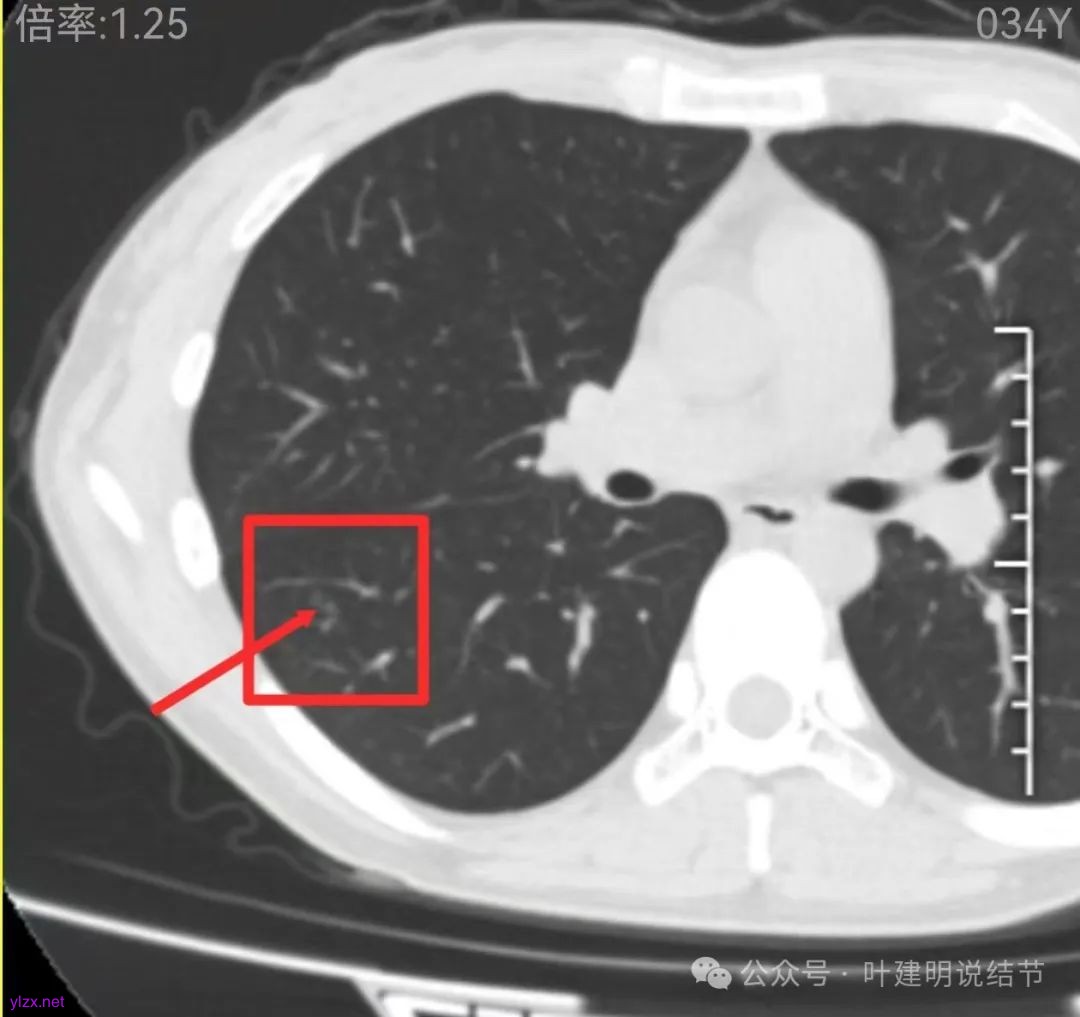

右下叶磨玻璃结节伴空泡征,轮廓较清,瘤肺边界清楚。

表面不平,轮廓较清,有血管进入,边缘略显毛糙。

病灶内有少许偏实性成分,与血管关系较为密切,局部似有浅分叶的样子。

这层面看,密度不纯,部分区域的边缘有细毛刺征。但感觉与前一层面的结节形态不似延续过来的。

边缘区密度也略显高,圆形的样子。

两肺多发结节,左侧黄色标注的考虑是肺泡上皮增生可能性大;蓝色的考虑肺泡上皮增生或者少许慢性炎可能性大;右侧红色宽起来并带有红色箭头的这处是主病灶,偏混合密度,整体轮廓较为清楚,边缘显得毛糙,从2024年12月份的来看,要考虑是肿瘤范畴,原位癌或者微浸润性腺癌可能性较大,也不能完全排除不典型增生。但是在2022年的时候,这个病灶的边上也有一个实性的微小结节,如果只看2022年的,这么小的实性结节,又比较圆,表面也显得较为光滑,是要考虑良性的,当然太小了需要动态观察。回头再重新来看2024年底的,发现绿色箭头所指的这个微小实性的较2022年几乎没有变,去仔细寻找2022年的,发现当时在实性结节旁边也有密度很淡的一点磨玻璃影(也可能真的就是一处,只是扫描不够薄,密度的变化有些突兀而已),而到了2024年12月份,实性微小这处没有明显变化,但是原来很淡的磨玻璃变成了混合磨玻璃,范围也明显扩大。所以总体来看右肺下叶这处是考虑恶性的,而且从磨玻璃结节角度来讲,还是生长比较快的,就是说还是有一定风险的。加上左侧还有两处也是磨玻璃持续存在,虽然边缘轮廓显模糊一点,但多年以后也可能仍然要变成原位癌或者微浸润性腺癌之类的东西。通盘考虑以后,我倾向于右侧近期单孔胸腔镜下微创局部切除,左侧随访观察,等到有进展并风险增加再来考虑处理。意见供参考!